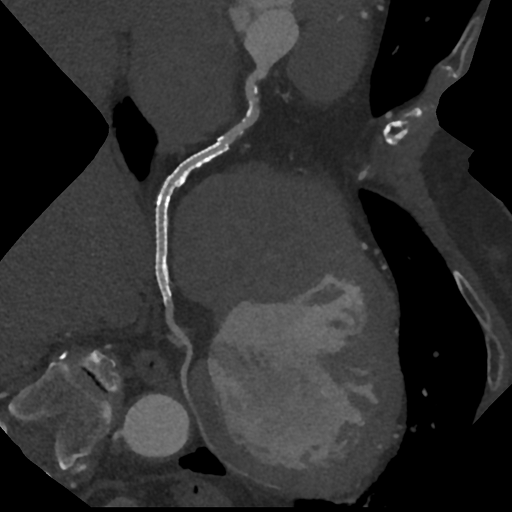

PCI後の冠動脈評価CT

PCI施行前と後

CTでは、心臓に酸素や栄養を送る冠動脈と呼ばれる血管の状態(狭窄や閉塞)や、心臓の全体像を知ることができます。また、バイパスなど手術後の経過なども調べることができます。